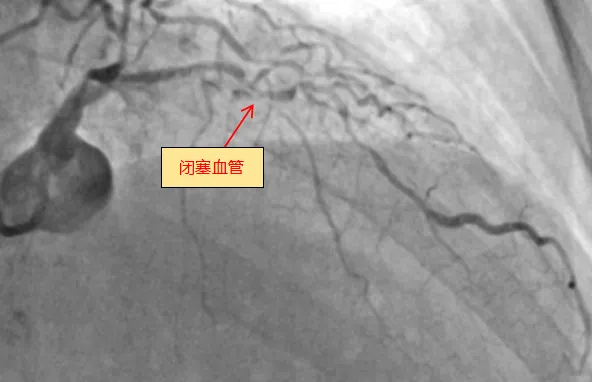

6月13日,小妲己直播app (简称小妲己直播app )心血管内科团队成功完成全新ROTAPRO™旋磨介入治疗系统上市后在广西的首次应用,为一名复杂高危严重钙化患者进行了精准冠脉介入治疗,顺利开通闭塞的冠脉血管并完成支架植入。71岁的梁阿姨(化名)去年外院冠脉造影诊断为冠心病,三支血管严重狭窄,于右冠植入一枚支架,前降支严重钙化病变尝试开通失败。近几个月来,她反复出现胸痛症状...